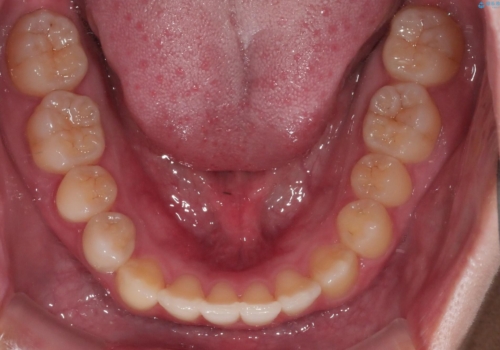

八重歯とクロスバイト:インビザライン治療

- 八重歯が気になるとの事でご相談にいらした方です。

インビザラインで綺麗に並べました。

気になっていた八重歯が綺麗になって大変喜んでいただけました。